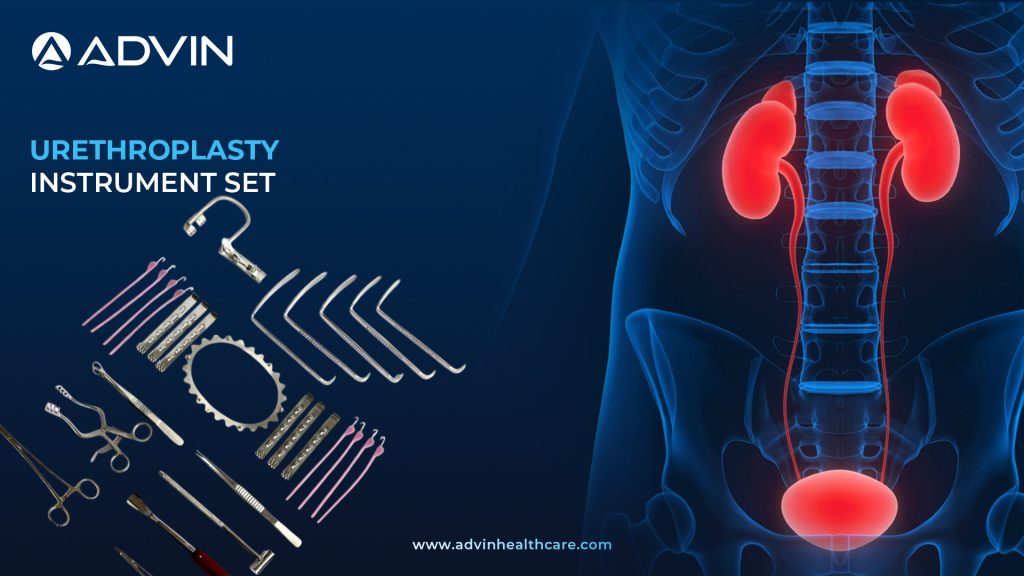

Urethroplasty Instrument Set – Complete Instrumentation for Effective Stricture Repair

Introduction to Urethroplasty Instrument Set: Specialized Tools for Reconstructive Urology The Urethroplasty Instrument Set is used in reconstructive urology to repair or replace narrowed sections of the urethra. This set includes essential surgical tools designed for precision, control, and effective dissection. It is commonly used during urethral stricture surgeries. Evolution...